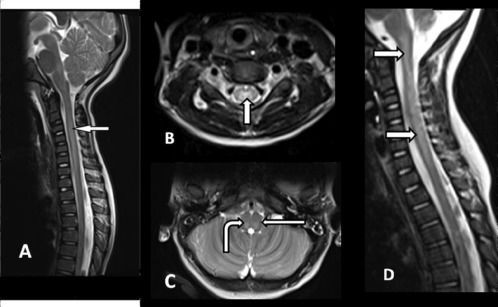

Acute flaccid myelitis (AFM) is an uncommon but serious neurologic condition. It affects the nervous system, specifically the area of the spinal cord called gray matter, which causes the muscles and reflexes in the body to become weak. Increases in AFM cases have occurred in 2014, 2016, and 2018 in the U.S.